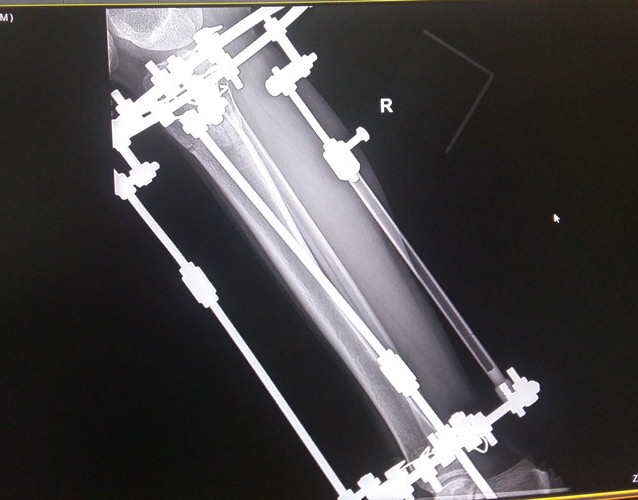

Рентген в 81 день с момента операции.

Здравствуйте, Соломея! По рентгену, у Вас всё отлично! В 90 дней возможно снятие аппаратов. Натаптывайте интенсивно ножки все эти дни, но без фанатизма(ведь когда я Вам говорю больше ходите- это значит, что при физ нагрузке быстрее разрастается костная ткань - вырабатывается, наступает сращение) лучше приехать и остаться у нас в клинике до снятия аппаратов. Один раз можно пожертвовать временем, расстоянием и средствами ради благополучия и отличного результата! Ножки мы исправляем один раз и навсегда!